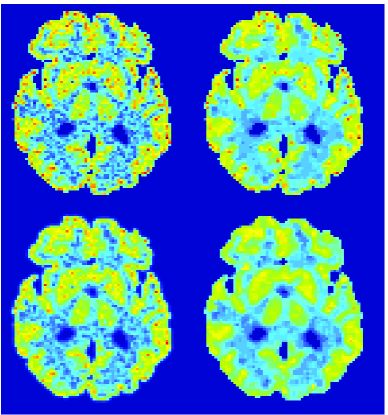

In figure 5 we illustrate the relative error of noisy case for gray matter regions in the phantom, including frontal lobes, occipital lobes, insula cortex, temporal lobes and globus pallidus, which are of interest for Alzheimer’s disease research. The error bars show that all estimation methods for gray matter regions have negative bias and there are fewer cases with high error by TV-Patlak.